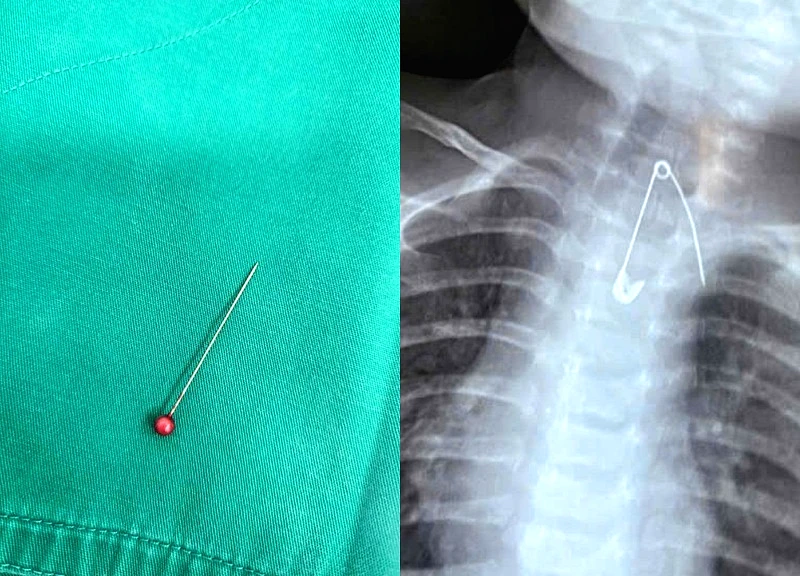

Giành lại sự sống cho bé 13 tháng tuổi mắc kim ghim trong phế quản